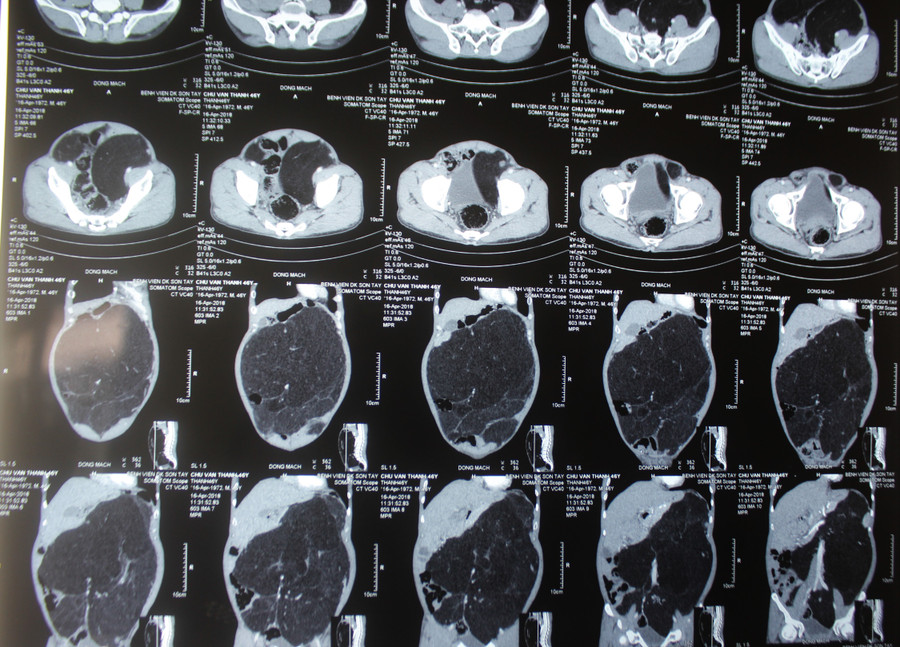

| Khối u khủng sau khi được lấy ra |

Đúng như chẩn đoán, khối u chiềm toàn ổ bụng, kích thước rất lớn đè đẩy vào các tạng, u xâm lấn vào đại tràng và niệu quản trái. Sau gần 5 giờ phẫu thuật, kíp mổ với các y bác sĩ giàu kinh nghiệm, phẫu tích tỉ mỉ đã tiến hành cắt bỏ hoàn toàn khối u nặng tới 10,5 kg; đường kính hơn 40cm, cắt đoạn đại tràng trái và đại tràng sigma, cắt đoạn niệu quản trái, nối lại niệu quản trái bảo tồn thận trái, lách, các mạch máu lớn( động mạch chủ bụng, mạc treo tràng trên…).